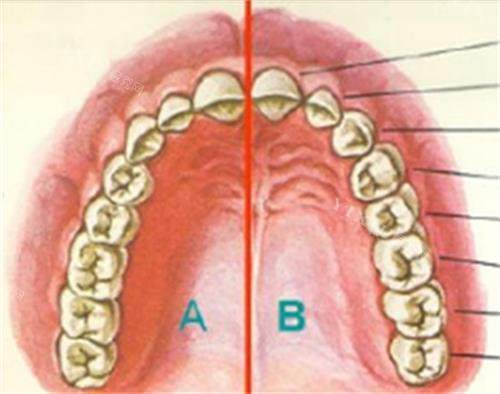

穿颧穿翼种植牙作为口腔种植领域的“技术”,专为上颌骨重度萎缩、骨量不足的患者设计。这项技术通过将种植体植入颧骨或翼板骨,实现“无土栽培”般的稳固结果,但价格也因技术难度和材料成本较高。